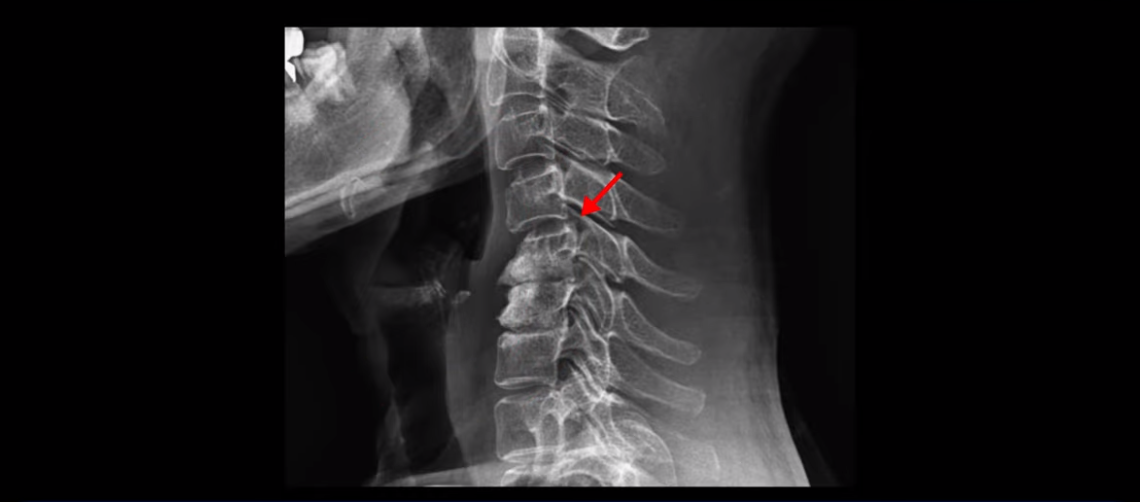

이분 목 X-ray를 보면 역C자형의 목에 전방전위도 보이고,

두 마디의 디스크가 거의 닳아서 뼈들이 거의 붙어 보입니다.

목도 많이 휘어 보입니다.